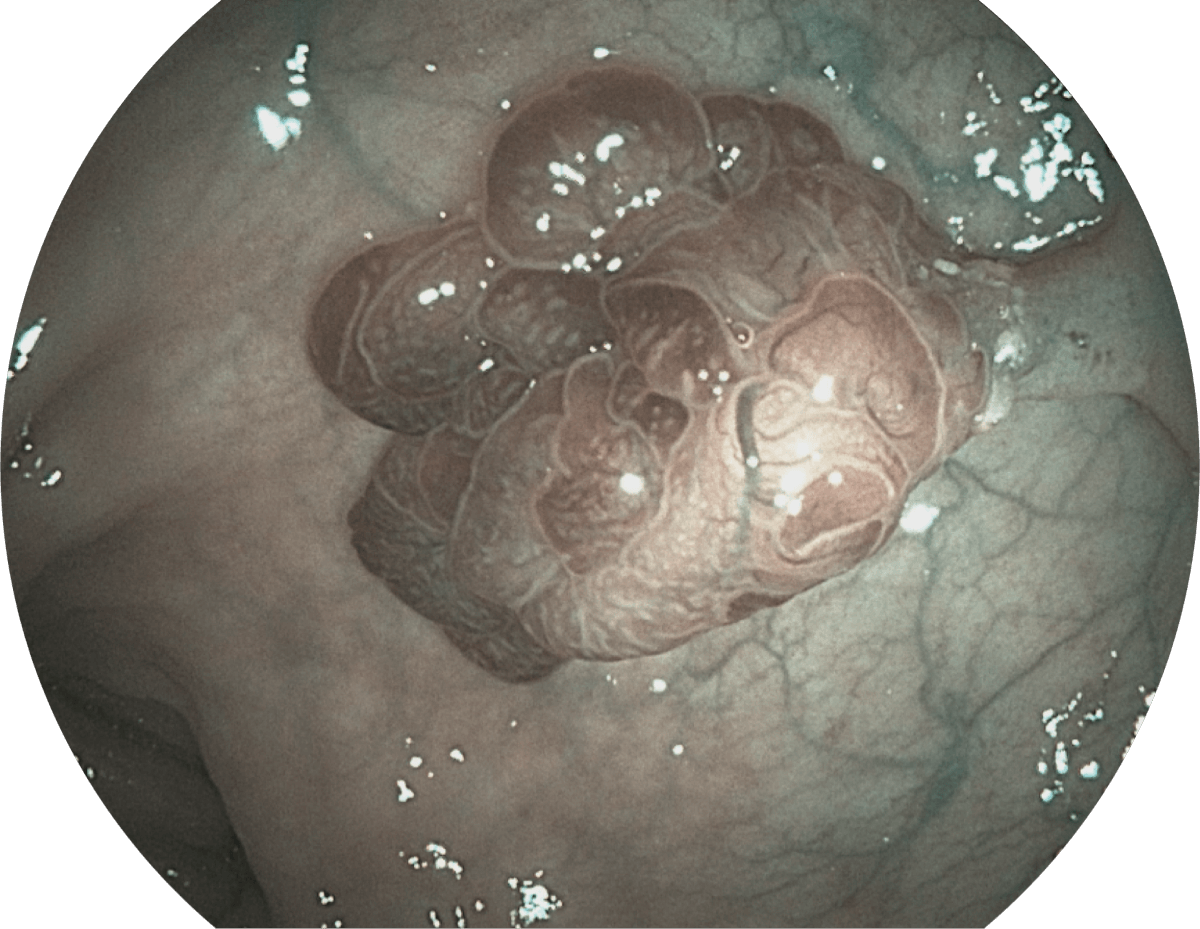

( Versatile Intelligent Staining Technology, VIST )

强调浅层黏膜结构的同时,保证照明亮度和提升浅层微血管与中层血管颜色对比度,病变边界更清晰。

• WL

• SFI

• VIST